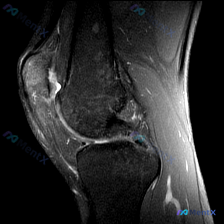

本次提供的是膝关节MRI T2序列轴位图像,主要显示髌股关节层面,影像观察结果如下:

- 髌骨软骨:髌骨外侧关节面软骨信号不均匀,局部信号增高、厚度不均,软骨轮廓欠光滑;髌骨软骨下骨骨髓信号未见明显异常

- 髌股关节腔:关节间隙内外侧均可见高信号积液影,积液量较明显

- 周围软组织:髌骨周围支持带未见明显断裂或弥漫性严重水肿,仅存在非特异性信号改变,无占位性病变

- 股骨髁与滑车:骨髓信号无异常高信号(骨挫伤)或低信号(骨折线),无其他明显结构异常